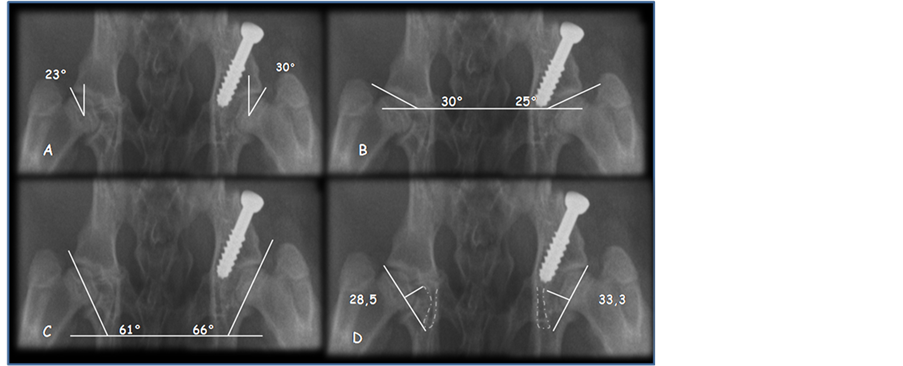

When comparing the median differences of the angles between groups evaluated at 12 weeks, a statistically significant difference was found in all radiographic measurements: an increase in Wiberg’s angle but a decrease in Acetabular index, acetabular angle of Sharp, acetabular depth index, and acetabular anteversion.

The differences of the results between groups are shown in Table 2 (Figure 8).

Figure 8. Radiographs of 12-week-old rabbits comparing right group-1 hips with left group-2 hips. (A) Lateral center-edge angle; (B) Acetabular index; (C) Angle of Sharp; (D) Acetabular depth index.